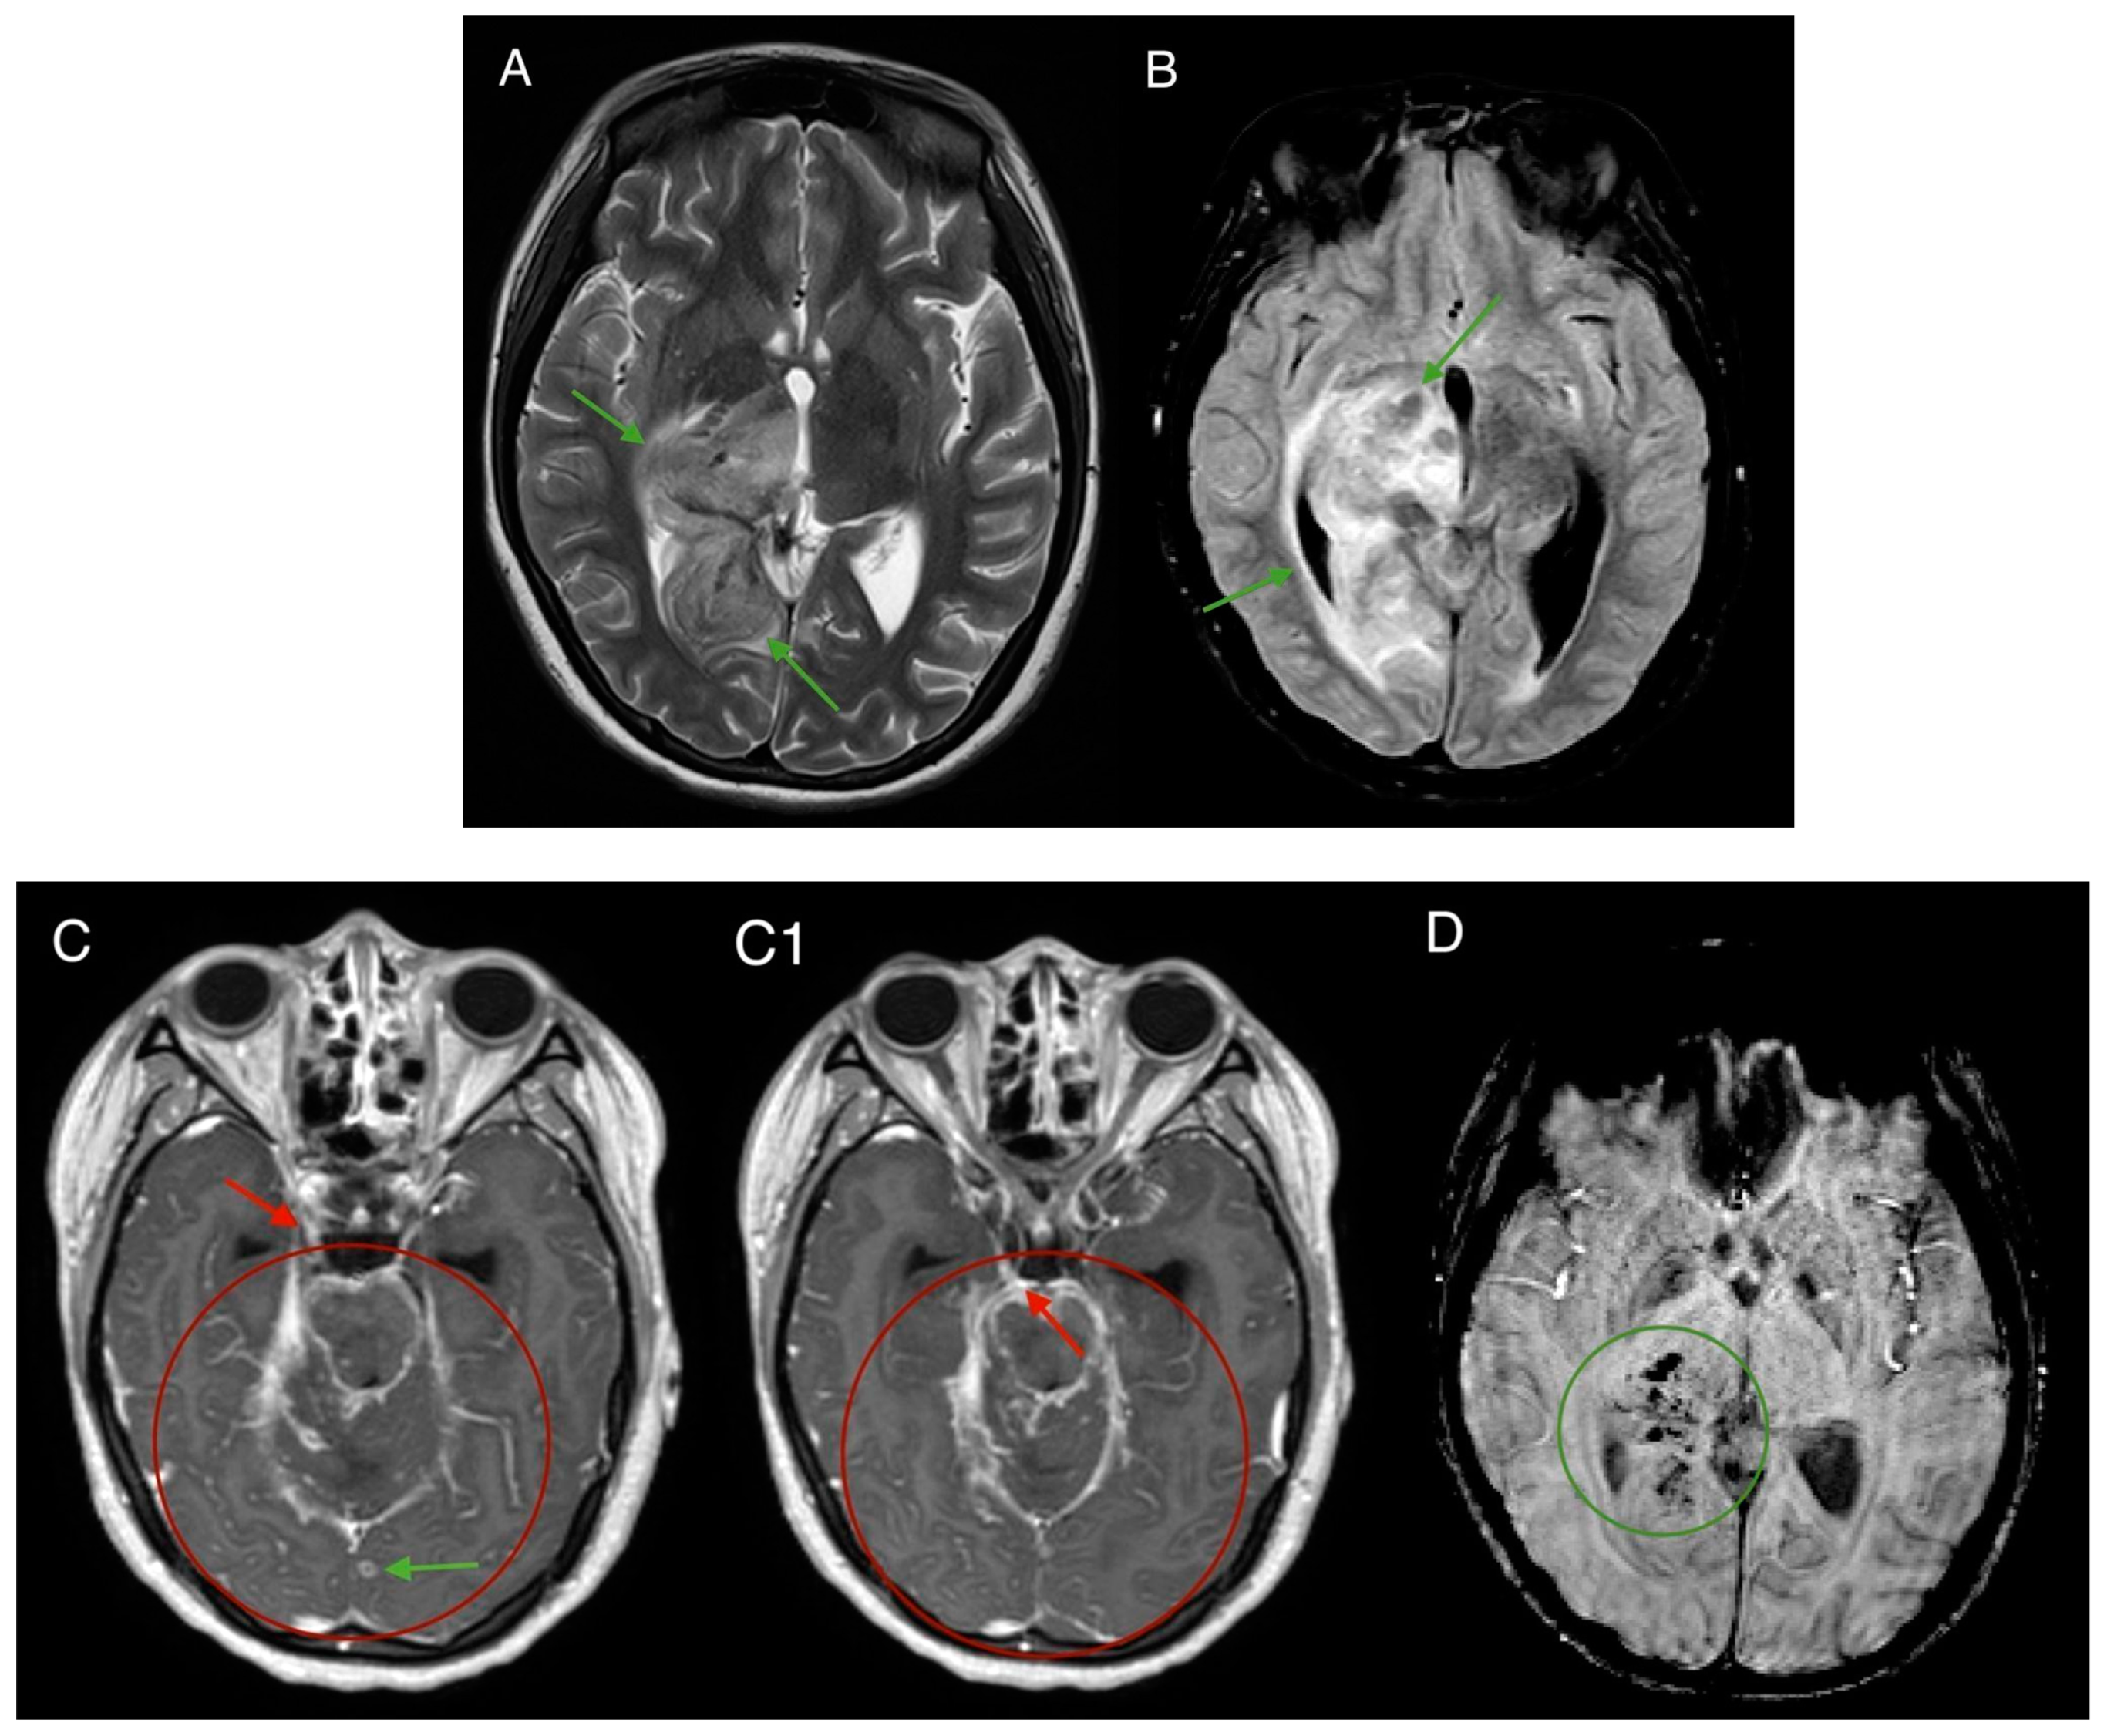

2. Case Report